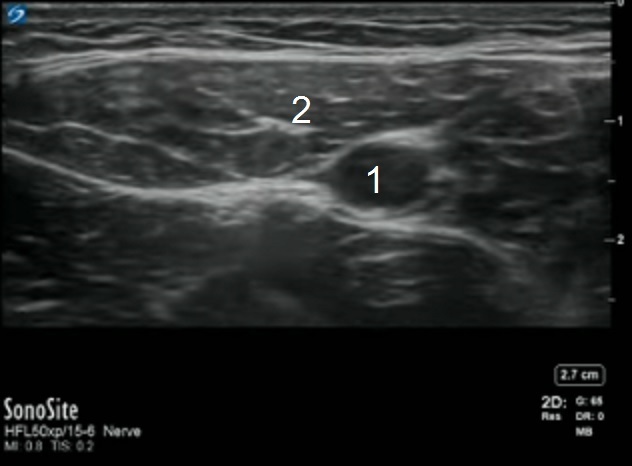

Adductor Femoral Artery Location Image

Femoral Artery

Sartorius Muscle